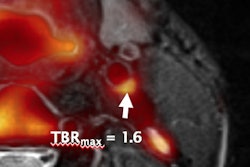

Since its first commercial installation in 2011, the number of facilities housing PET/MRI systems has increased to 70 worldwide, according to the paper. The near-simultaneous acquisition of PET's molecular images and high-resolution anatomical MR images of soft-tissue contrast has been the enticing lure of the modality.